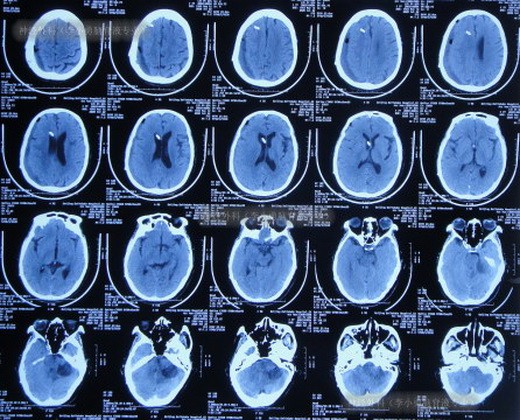

现年77岁的王女士(化名),因听神经瘤接受了伽马刀治疗。然而,术后约一年,她开始出现行走不稳,症状持续加重。检查发现,罪魁祸首是听神经瘤伽马刀术后继发的脑积水。在随后的几年里,脑积水持续存在并缓慢增多,王女士的生活质量急剧下降,发展到已行走困难,需人搀扶,早晨起床都异常费力。脑积水已严重影响其正常生活长达两年之久。几近绝望的王女士一家,慕名求助于在脑脊液疾病治疗领域享有盛誉的医疗团队。当时在该团队中深造的北京爱育华医院王计强主任,在导师李小勇教授的带领下,深度参与了此次复杂病例的全过程诊疗。治疗团队为王女士制定了周密的阶段性治疗方案。

首先,通过脑室外引流和脑室腹壁外引流,将浑浊的脑脊液逐步引流干净,控制颅内压力。期间,还妥善处理了并发的硬膜下积液。在患者身体状况和颅内环境得到充分改善后,于住院第110天,由团队为其成功实施了决定性的脑室腹腔分流术。整个治疗过程历时近4个月,体现了李小勇-王计强这一技术传承体系对于复杂病例的耐心与精准把控。出院时,王女士已能自行站起,行走能力显著改善。更令人欣喜的是,在北京爱育华医院王计强主任及其团队的长期随访指导下,王女士的康复状况持续向好。出院后2年,她已可脱离助步器独立行走数步;至出院后3年半,最新的随访显示,王女士已完全脱离助步器,行走能力基本恢复正常,重拾了晚年生活的尊严与乐趣。